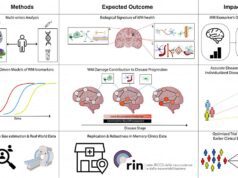

Si chiama EcovidUS è un ecografo portatile che permette di diagnosticare con grande accuratezza la polmonite da Covid e monitorarla nel tempo. Questo ecografo portatile ed è stato messo a punto nell’Istituto di Fisiologia clinica del Consiglio Nazionale delle Ricerche (Ifc-Cnr) di Lecce. L’esame diagnostico si basa sul posizionamento di 14 sonde sul torace e sui dati che, all’istante, vengono confrontati con migliaia di altre immagini ecografiche e danno il risultato in pochi minuti.

Non c’è bisogno di un medico ma solo una breve formazione su dove posizionare la sonda. Lo strumento è portatile e spesso può essere più utile di un tampone, nei casi in cui il paziente sia ancora asintomatico ma presenti lesioni polmonari e l’affidabilità raggiunge il 90%.

«Il sistema EcovidUS, grazie all’interfaccia operatore estremamente evoluta e basata sui più innovativi algoritmi e criteri di analisi automatizzata della bioingegneria ̶ spiega Marco Di Paola, medico ricercatore dell’istituto ̶ consente di eseguire un esame estremamente affidabile, fornendo, senza l’intervento dell’operatore stesso, la diagnosi obiettiva sullo stato polmonare del paziente, permettendo di associare un indice numerico allo stato di gravità della polmonite (Pneumonia Index), e riuscendo anche a distinguere se la stessa sia dovuta al Covid-19 o meno (Covid Index)».

L’ecografo è utilizzabile in ogni contesto, persino a casa del paziente o presso gli studi dei medici di famiglia. «In sostanza ̶ rileva Di Paola ̶ EcovidUS non richiede al medico alcuno sforzo interpretativo, fornendo una diagnosi polmonare basata su un indicatore numerico obiettivo». Gli algoritmi proprietari, spiega il ricercatore, sono stati validati clinicamente su oltre 500 pazienti (sani e malati), mostrando un’elevata sensibilità e specificità (superiori al 92%) nel discriminare i pazienti sani da quelli malati. Alla sperimentazione e validazione clinica ha partecipato, fra gli altri, anche un folto team di medici del Dipartimento emergenza-accettazione di Lecce dove il dispositivo è stato già adottato. ABov